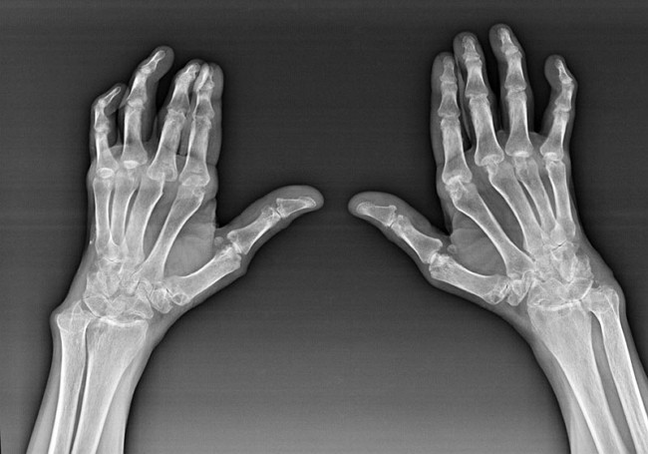

Reimatoīdais artrīts

Reimatoīdais artrīts ir slimība, kurā cilvēka imūnsistēma sabojā paša ķermeņa audus. Citiem vārdiem sakot, reimatoīdais artrīts ir autoimūna patoloģija. Šī slimība ir arī sistēmiska, jo ar to ietekmē daudzi audi (Muskuļi, locītavas, trauki utt.) un orgāni (Sirds, nieres, plaušas utt.) ķermenī.

Neskatoties uz to, ka reimatoīdais artrīts ir sistēmiska slimība zem tās, lielākā mērā cieš locītavas, kamēr fonā ir citu audu un orgānu bojājums. Ar šo slimību var ietekmēt gandrīz visu veidu suku locītavas (plaukstas sienas, karpalas, metakarpal-phalanksa, starpphalanksa locītavas). Bojājums parasti ir simetrisks (tie. Tās pašas locītavas tiek ietekmētas) Uz abām rokām, ko papildina pietūkums, sāpes bojātās locītavās. No rīta, paceļot no gultas, skartajos locītavās ir zināma stingrība, kas var ilgt apmēram 1 stundu un pēc tam pazust bez pēdām.

Diezgan bieži ar reimatisku artrītu netālu no skartajām sukas locītavām (Biežāk klavieres-phalanksa, starpphalanksa locītavas) Parādās reimatoīdi mezgliņi. Tie ir noapaļots veidojums, kas atrodas zem ādas. Uz sukas šie veidojumi visbiežāk rodas aizmugurē. Palpē tie ir blīvi, neaktīvi, nesāpīgi. To skaits var atšķirties.